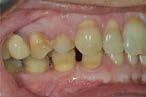

Case treated with EF TMJ

• Skeletal Class I • Hyperdivergent facial typology • Severe anterior DMD

• Skeletal Class I • Hyperdivergent facial typology • Severe anterior DMD Wearing of an EF TMJ then an EF guide Before wearing EF TMJ